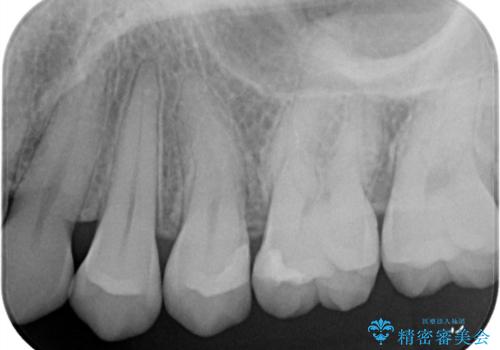

- クリーニング時に治療が必要な大きさの虫歯が見つかりました。

審美性と材料の安定性からセラミックでの修復を行うこととなりました。

う蝕を除去し、CRにて裏層をし、セラミックインレーにて修復しました。

ラバーダム防湿をした上で、接着しました。